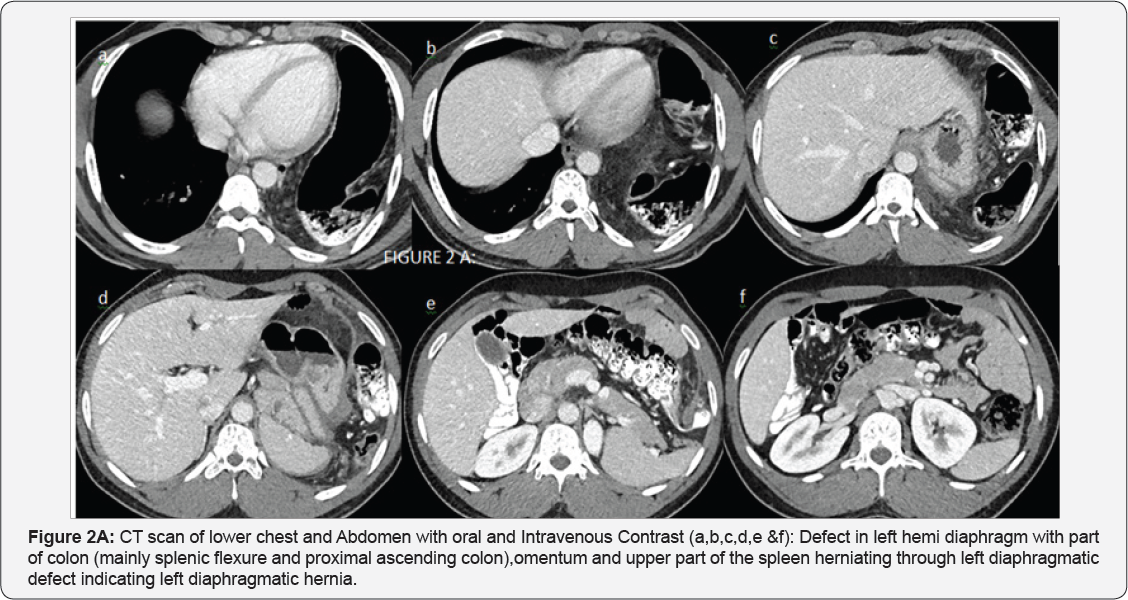

CT SCAN with Oral and IV contrast recommended for further work-up and characterization at time of first presentation after X-ray:

Impression of Figure 2A & 2B: Left diaphragmatic hernia containingpart of colon (mainly splenic flexure and proximal ascending colon),omentumand upper part of the spleen. No signs of acute bowel obstruction. No ascites. No free air.